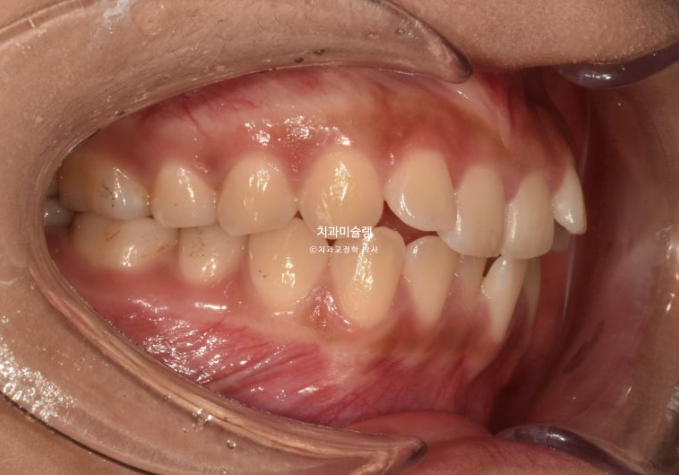

우측 교합관계는 1급에 가깝지만

좌측 교합관계는 2급입니다.

위 아래 치아들이 일대일로 물리면 2급 또는 3급 교합관계 입니다.

송곳니에서 큰어금니까지 절반씩 엇갈려 물리는 교합이 1급 교합입니다.

사랑니를 빼고 사랑니 공간으로 어금니를 후방이동 시켜 교합관계를 맞추고 덧니 해소할 공간을 얻기로 합니다.

돌출이나 뻗침은 없어서 비발치로 진행하는 것 입니다.